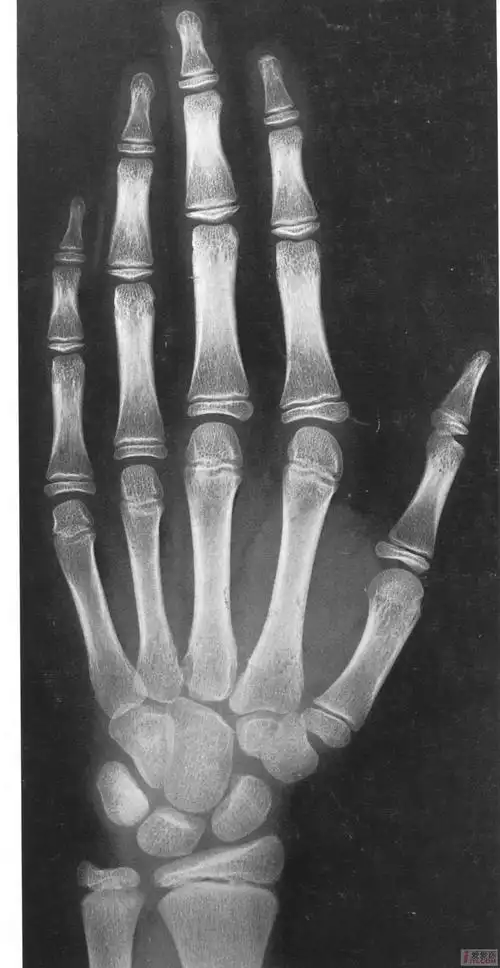

中国儿童标准骨龄片